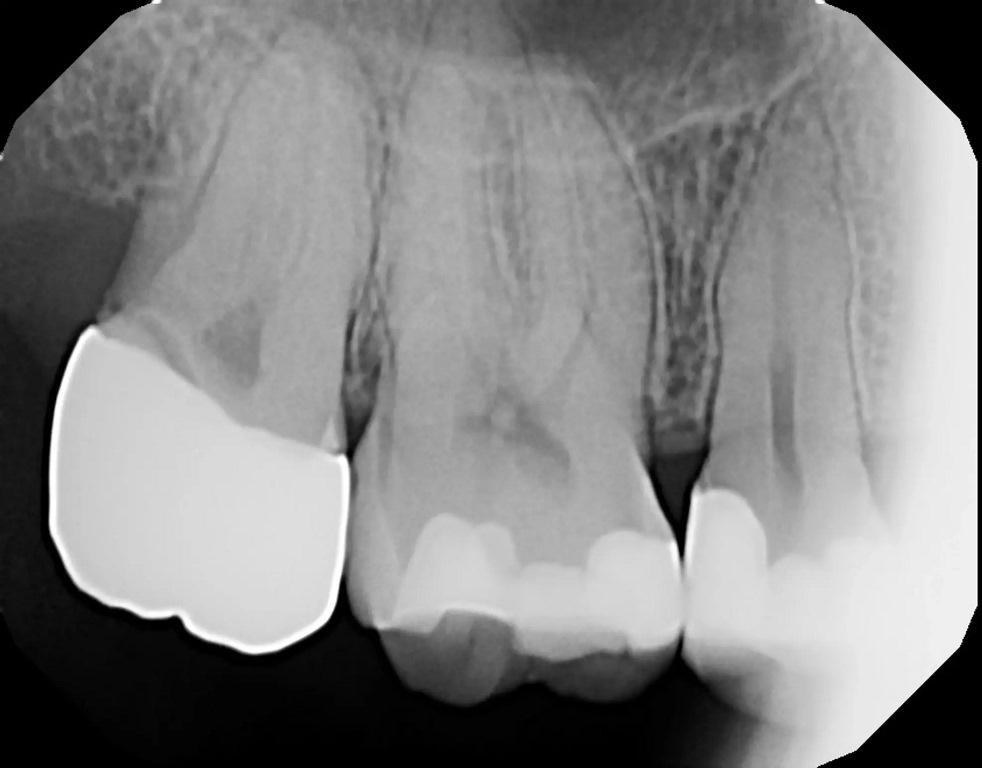

53-летня пациентка обратилась с жалобой на боль в левом квадранте верхней челюсти. Клиническое обследование выявило отсутствие лингвального бугорка на втором премоляре, а также кариес. Была сделана периапикальная рентгенограмма (фото 13). Глубокий кариес был подтвержден рентгенологически, и большая часть коронки была рентгенопрозрачной, что указывало на обширный кариес. Рентгенологически можно было различить контуры коронковой пульпы, но было отмечено отсутствие периапикальной патологии. Чтобы убедиться в жизнеспособности пульпы зуб подвергли испытанию холодом (фриз-тест). При проведении фриз-теста была отмечена слабая реакция, которая немедленно прошла, когда холод был удален с зуба, что указывало на то, что зуб был жизненно важным. Пациентке сообщили, что в результате удаления кариеса ожидается обнажение пульпы и потребуется эндодонтическое лечение. После предполагаемого эндодонтического лечения в зуб будет установлена штифтовая культевая вкладка и будет реставрация полной коронкой. Пациентка согласилась на рекомендованное лечение.

Фото 13: Периапикальная рентгенограмма, демонстрирующая обширный кариес на зубе №25 и отсутствие периапикальной патологии.

В буккальном преддверии ввели местный анестетик. Кариес и пораженная структура зуба были удалены с помощью твердосплавных и алмазных боров. Было отмечено очень небольшое обнажение пульпы (фото 14). После обсуждения с пациенткой вариантов немедленного эндодонтического лечения или лазерной обработки обнажения и установка вкладки с последующей установкой коронки (при условии, что в течение следующих нескольких недель не возникнет никаких симптомов), пациентка выбрала лазерное лечение пульпы. Nd:YAG-лазером в режиме абляции была проведена лазерная обработка поверхности пульпы после удаления кариеса при 50-75 Дж (фото 15). Затем в тех же настройках использовали лазер мощностью до 162 Дж для стерилизации окружающих структур зуба и биостимуляции, как описано в двух предыдущих клинических случаях. С лингвальной стороны в дентин был введен стабилизирующий штифт, чтобы помочь стабилизировать образование вкладки. Для покрытия нижележащей пульпы было нанесено небольшое количество стеклоиономерного цемента GC FujiCEM. Затем на окружающую здоровую структуру зуба был нанесен самоадгезивный композитный цемент RelyX Unicem (3M ESPE), чтобы обеспечить хорошее сцепление материала культи с дентином (фото 16). Подготовка коронки была завершена. Был сделан слепок, изготовлена временная коронка и зацементирована с помощью цинкоксидэвгенольного цемента IRM (Dentsply Sirona). Пациентка вернулась для послеоперационного осмотра зуба через неделю и сообщила об отсутствии какой-либо чувствительности к температуре или окклюзии временной коронки. Слепок был отправлен в лабораторию для изготовления коронки. Затем, через две недели, пациентка вернулась для окончательной установки коронки и по-прежнему отмечала отсутствие чувствительности. Временная коронка была снята, на окончательная коронка была установлена с помощью самоадгезивного композитного цемента RelyX Unicem, проверена и скорректирована окклюзия.

На повторном осмотре после лазерного лечения пациентка еще раз подтвердила отсутствие чувствительности к температуре или окклюзии. Была сделана периапикальная рентгенограмма, на которой не было отмечено рентгенопрозрачности периапикальной области, что указывает на то, что лазерная обработка пульпы успешно помогла избежать эндодонтического лечения (фото 17).

Фото 17: Периапикальная рентгенограмма через четыре недели после лазерного лечения и реставрации зуба, демонстрирующая отсутствие периапикальной патологии с момента завершения лечения.